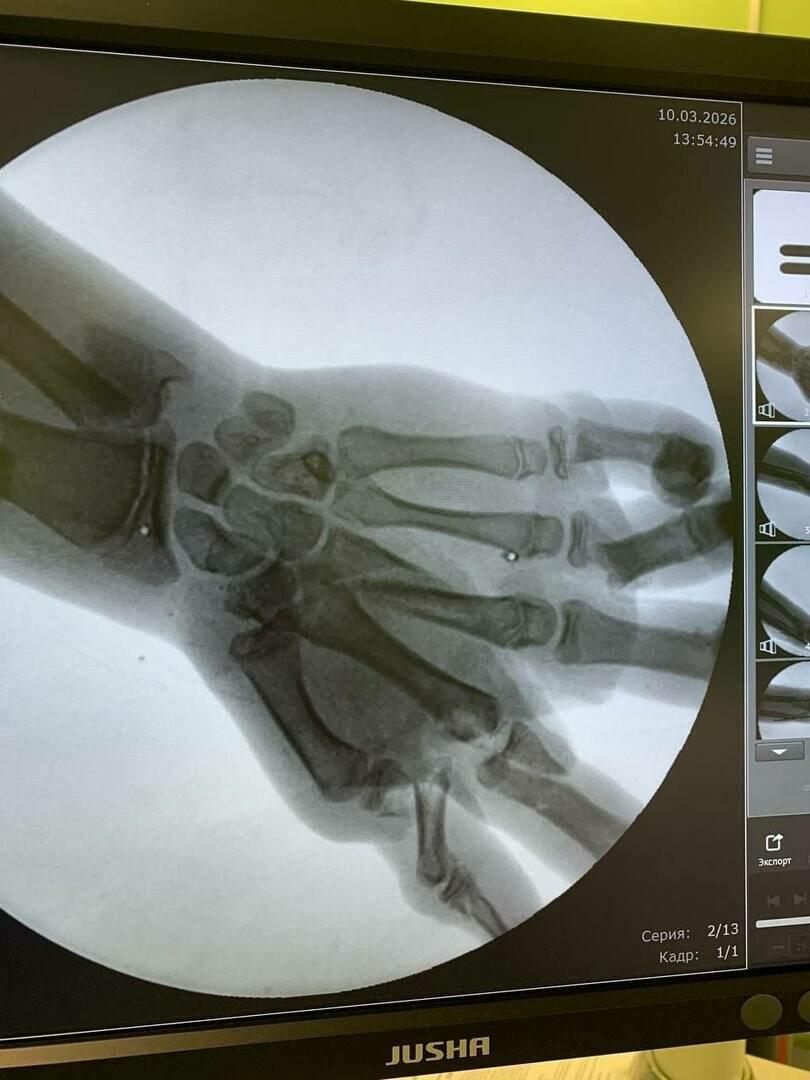

Врачи диагностировали перелом нижней трети левого предплечья со смещением, раны на голени и лбу, а также тяжёлые повреждения кисти с множественными переломами и сильным кровотечением.

Фото: минздрав Калининградской области